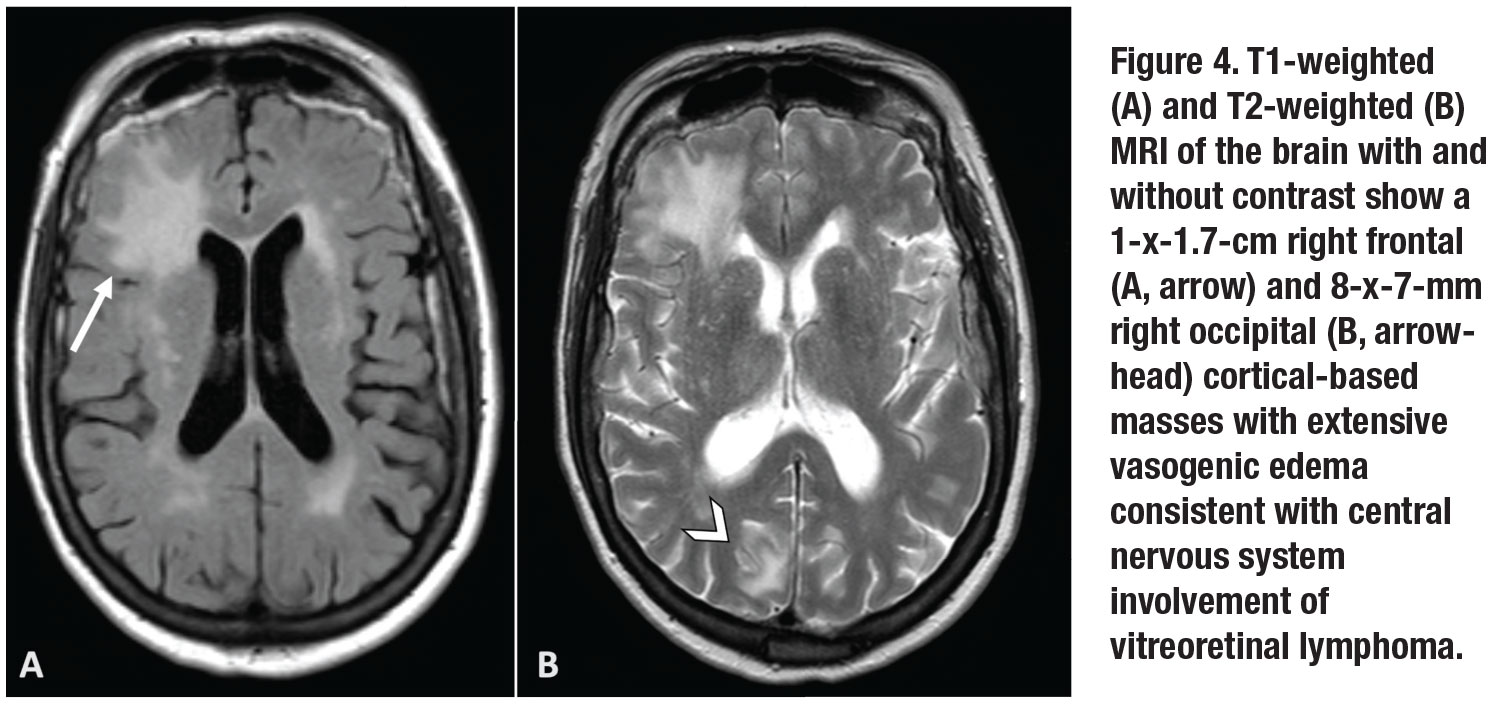

Further PCR testing of the subretinal material demonstrated MYD88 L265P mutation, supporting a diagnosis of vitreoretinal lymphoma. MRI of the brain and orbit revealed a 1-x-1.7-cm right frontal and 8-x-7-mm right occipital cortical-based masses with extensive vasogenic edema (Figure 4, page 13).